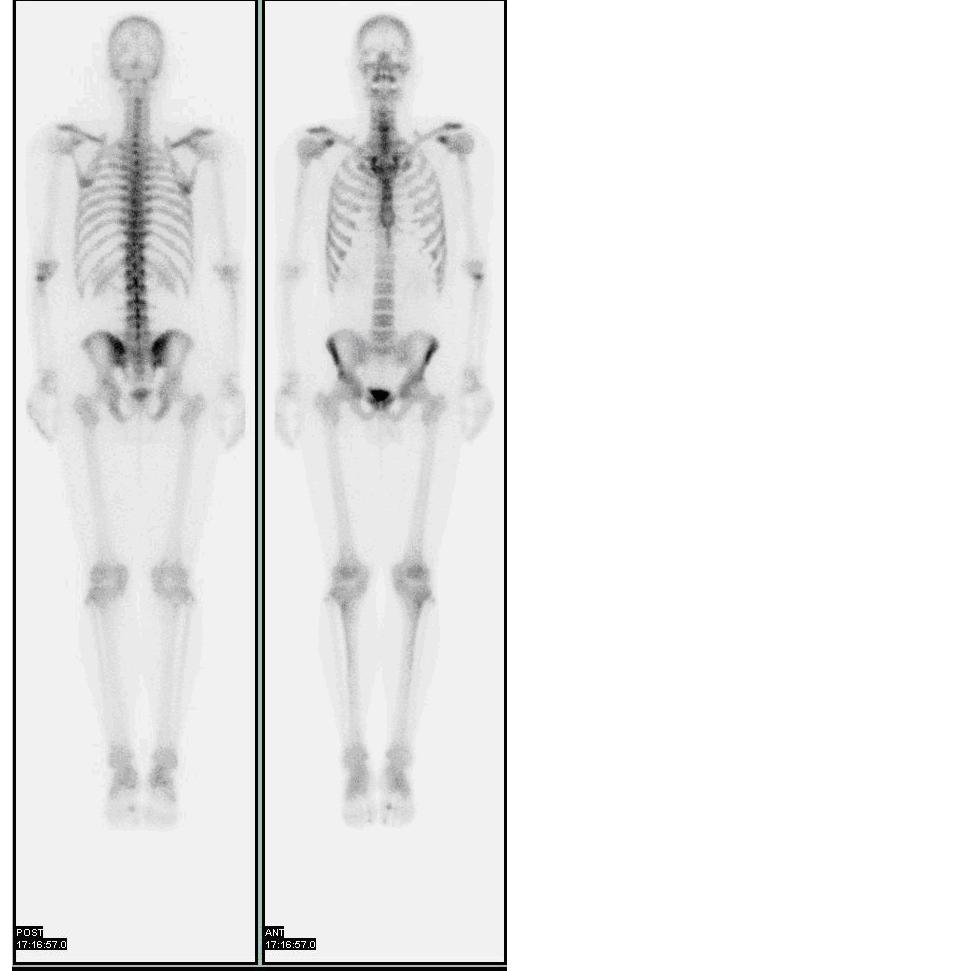

Get Nuclear Medicine Bone Scan Pictures. Your appointment letter will give you details of your appointment date and other useful information. Marcus r hall explains the basic steps of having a nuclear medicine bone scan for the benefit of the patients.

Your doctor may order a bone scan if you have you don't need to restrict your diet or avoid particular activities in preparation for a bone scan. Because the tracer contains a small amount of radioactive substance, a bone scan is referred to as nuclear medicine. Because nuclear medicine procedures are able to image the functions of the body at the molecular level, they offer the potential to identify disease in its earliest stages as well as a patient's response to therapeutic interventions.

Your physician may order a bone scan for bone pain, bone infection, injury or to evaluate for cancer. Let your doctor know if you've taken a medicine containing. Who should get a bone density scan? A bone scan is a nuclear medicine procedure that creates a picture of the metabolism of the bones.